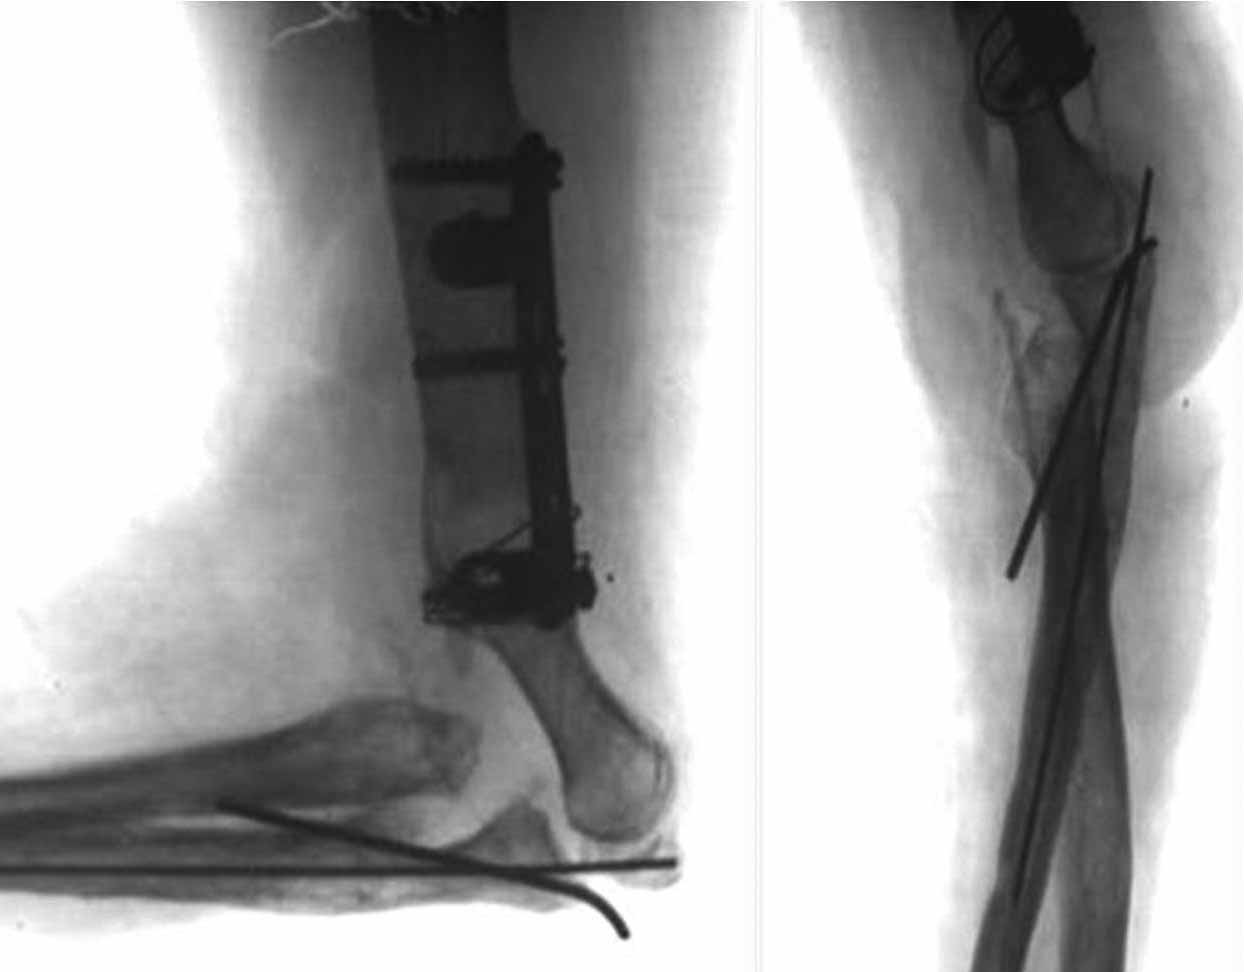

Как возможный вариант лечения, если от суставных поверхностей локтевого сустава ничего не осталось- это свободная пересадка васкуляризированного 1-го плюсне-фалангового сустава на сосудистой ножке из тыльной артерии в позицию локтевого сустава.